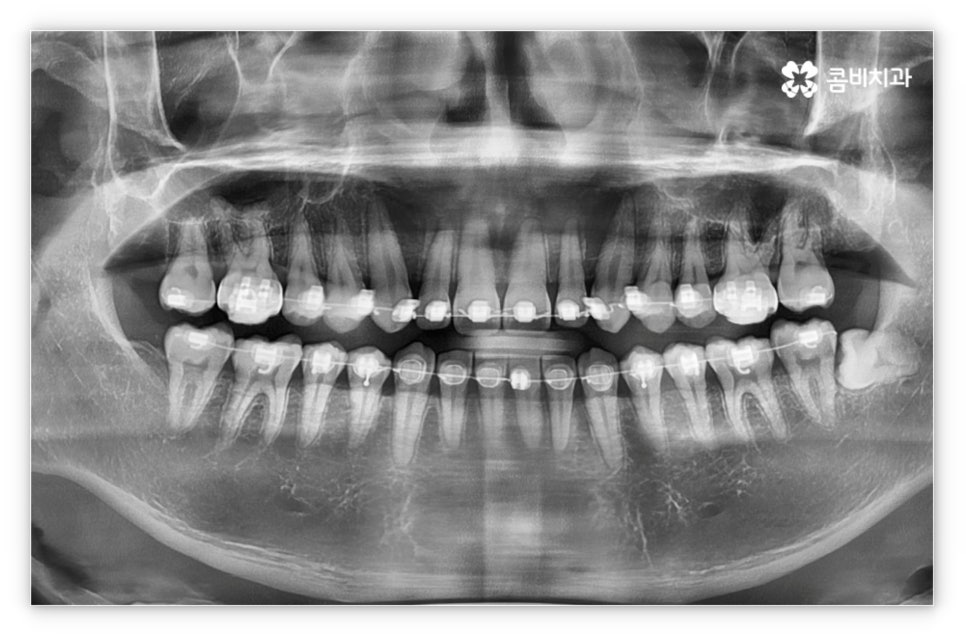

그리고 교정 치료는 그 목적상 위아래 교합이 똑바로 맞아 저작 기능을 제대로 수행할 수 있도록 하면서 가지런한 치열을 통해 발란스를 잡아주고 심미적으로도 좀 더 보기 좋은 안모를 형성하도록 하는 과정이기 때문에 환자의 치열과 교합, 얼굴 형태, 턱 관절 및 골격 구조 등 모든 부분을 세밀하게 파악하고 종합적으로 고려하여 각자에게 딱 맞는 교정 플랜을 세울 수 있도록 3D CT 와 같은 정밀 검진 기계를 갖추고 있는 치과에서 치료 받으시길 권유드리고 있는데요. 3D CT 는 일반 CT와 다르게 다각도에서 촬영을 하므로 환자분의 치아 위치, 턱관절, 얼굴의 정면 및 측면 등 다양한 정보를 수집하여 의료진 분들의 세밀한 파악을 돕는다는 장점이 있어요.

살펴본 바와 같이 앞니설측교정 의 장점에도 불구하고 아랫니 부분은 장치가 혀에 닿게 되기 때문에 환자분들께서 불편함을 느낄 수 있고 혹시라도 혀가 브라켓에 잘못 쓸리거나 눌렸을 때 통증이 발생할 수도 있으며 발음이 불분명해지는 문제가 생길 수 있는데요. 이러한 이유로 앞니설측교정 에 대해서 고민이 되시는 분들은 윗니 부분은 설측으로, 아랫니 부분은 일반 교정처럼 순측으로 진행하는 콤비 교정에 대해서 알아보시면 좋을 거예요. 위의 사진에서 살펴보실 수 있는 경우가 바로 이렇게 콤비 교정으로 진행한 환자분의 케이스인데 아랫니의 경우 보통 입술에 가려 별로 드러나지 않는 데다가 치아 색상인 세라믹 재질로 된 브라켓을 이용하기 때문에 설측 교정과 비교해도 심미성이 크게 떨어지지 않는다는 것을 알 수 있어요. 콤비 교정의 경우 설측 교정보다 비용적인 부담도 줄일 수 있으니 각 장치에 대한 장단점을 의료진분들과 충분히 상담하셔서 자신에게 맞는 장치를 선택하시면 좋을 거예요.